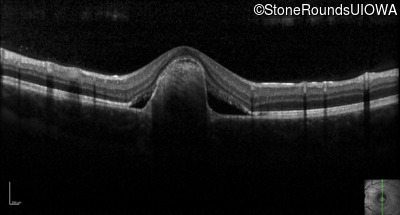

Visit at age: 16 years

Optical Coherence Tomography - Right - 20/40 +2 sc

Exemplar / OCT Stack